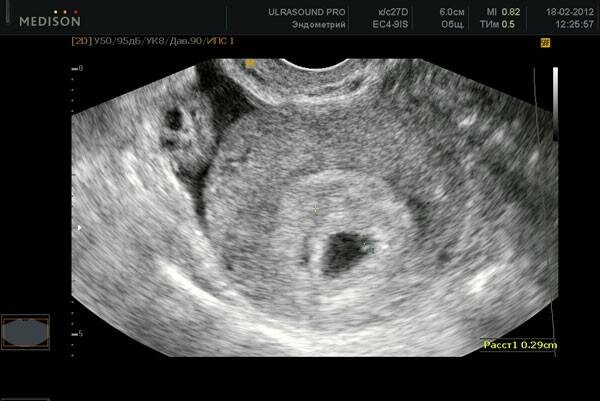

А вот УЗИ в этом сроке может выявить наличие желтого тела беременности в яичнике, которое будет постепенно увеличиваться в размере и поддерживать беременность до момента полного формирования плаценты. Постепенно гормональную функцию будет по мере роста плода и плаценты брать на себя именно она. А сам зародыш в матке сегодня могут определить только очень современные и высоко чувствительные аппараты, которые имеются далеко не во всех клиниках. Но УЗИ в этом сроке проводится по поводу беременности редко, только в особых случаях именно индуцированных беременностей.